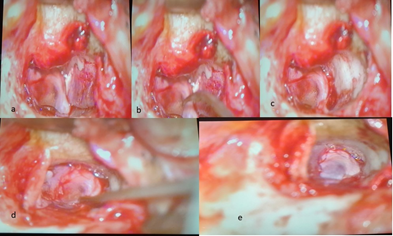

All surgical procedures were done under general anesthesia. A post-auricular approach was utilized in all patients and the temporalis fascia was used for grafting. Margins of perforation were freshened. Subsequently, a tympanomeatal flap was elevated from the posterior canal wall down to the annulus, preserving the fibrous annulus at its bony sulcus. This technique involves the division of the tympanomeatal flap by a single incision over the 9 o'clock position ( for right ears) and 3 o’clock position ( for left ears) and then splitting of the annulus, resulting in two canal-drum skin flaps referred to as "swinging doors." Superiorly and inferiorly-based swing-door flaps were then rotated anteriorly, allowing for a better view of the entire surgical field and facilitating the removal of any pathological tissues in the middle ear (Figure 1).

Figure 1 (a,b) Showing incision at 3 o’ clock for creation of “swinging door flaps”. (c,d) Showing superior and inferior flaps pushed anteriorly.